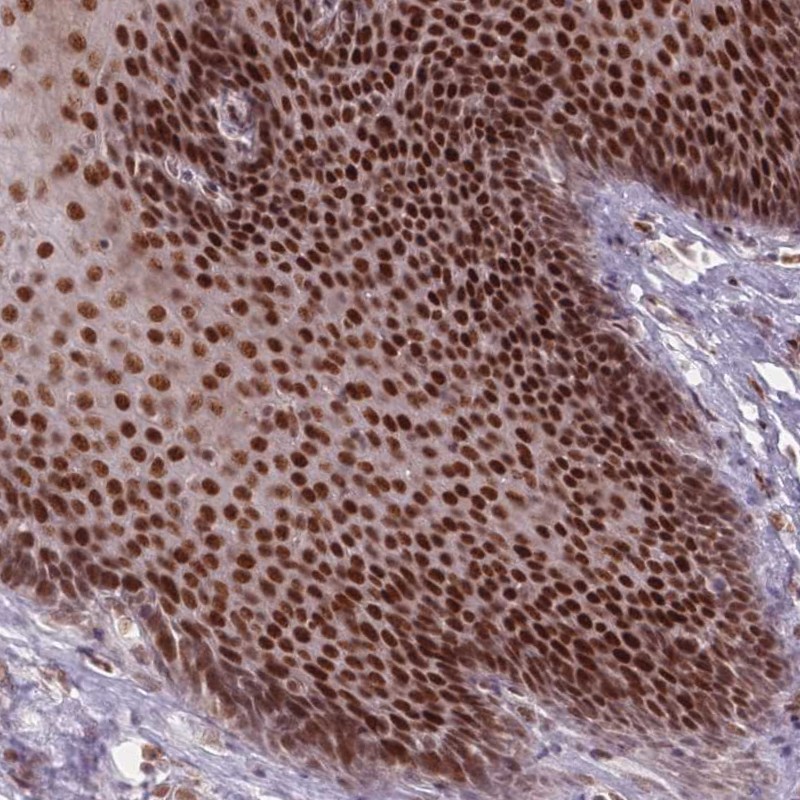

Immunohistochemical staining of human esophagus shows strong nuclear positivity in squamous epithelial cells.